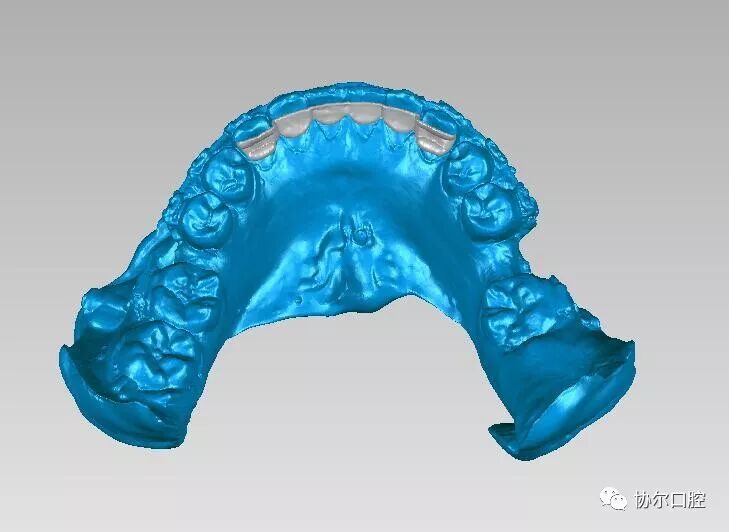

致力于3D打印技术在正畸临床运用中的研究,开创性的设计了舌侧夹板粘结式和舌侧TPA粘结式正畸增强支抗装置,运用于临床能够节省顾客的复诊时间和次数,精确性高,顾客佩戴更加舒适及便于临床医生的操作。